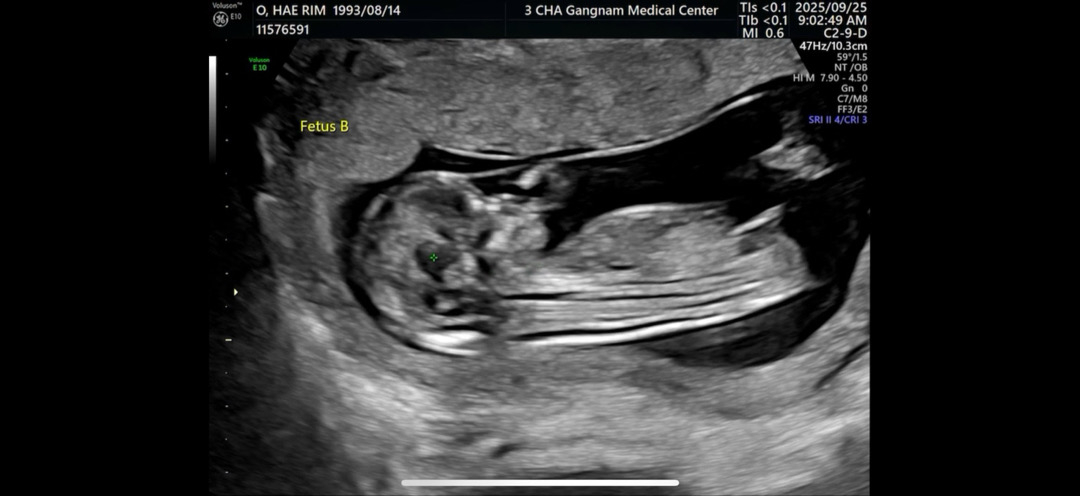

11주 5일차 각도법 봐주세요!!🙏

11주 5주차 각도법 한번 봐주세요!!!!